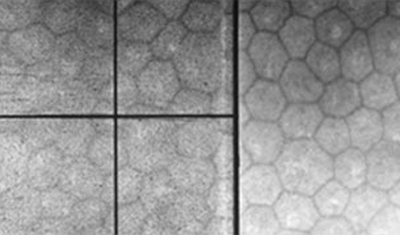

Endoteliografía

Endoteliografía

Siendo la capa más interna de la córnea, está en contacto con el humor acuoso y forma la pared de la cámara anterior; Está compuesta por células hexagonales distribuídas en una sola capa con una cantidad promedio de 2.500-3.000 células por mm2. Van disminuyendo con la edad. Permite el paso de nutrientes al interior de la córnea y controla su estado de deshidratación, siendo por lo tanto la capa responsable de mantener la transparencia corneal. El endotelio tiene muy escasa capacidad de regenerarse por lo que no es capaz de reparar por división un defecto en su extensión, lo cual hace agrandando y extendiendo sus celulas.